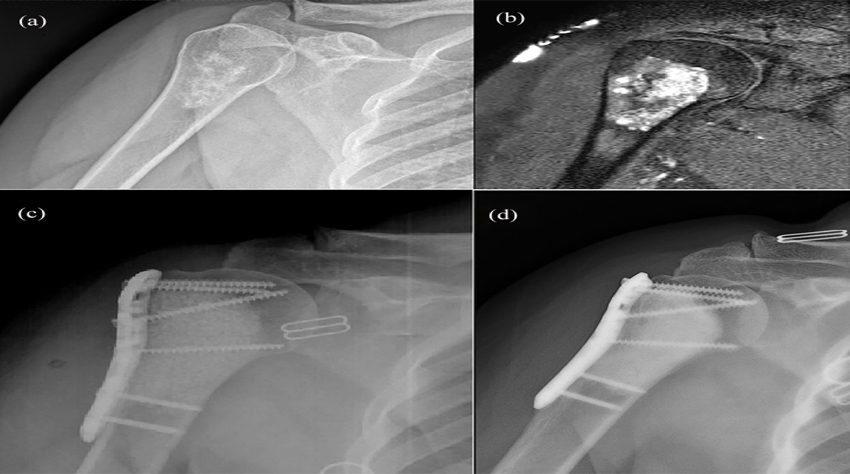

Devamı...Omuz çevresi tümörlerde ters omuz proteziReverse shoulder prosthesis for tumors around the shoulderVolkan Gürkan1 , Muzaffer Ağır2 , Fatih Yıldız3 1 Avicenna Umut Hastanesi, Ortopedi ve Travmatoloji Kliniği, İstanbul 2 Acıbadem Üniv...

Devamı...Harzem Özger1 · Bugra Alpan2 · Ahmet Salduz6 · Volkan Gurkan3 · Mustafa Sungur4 · Natig Valiyev5 · Levent Eralp1Bezmiâlem Vakıf University Faculty of Medicine, Department...